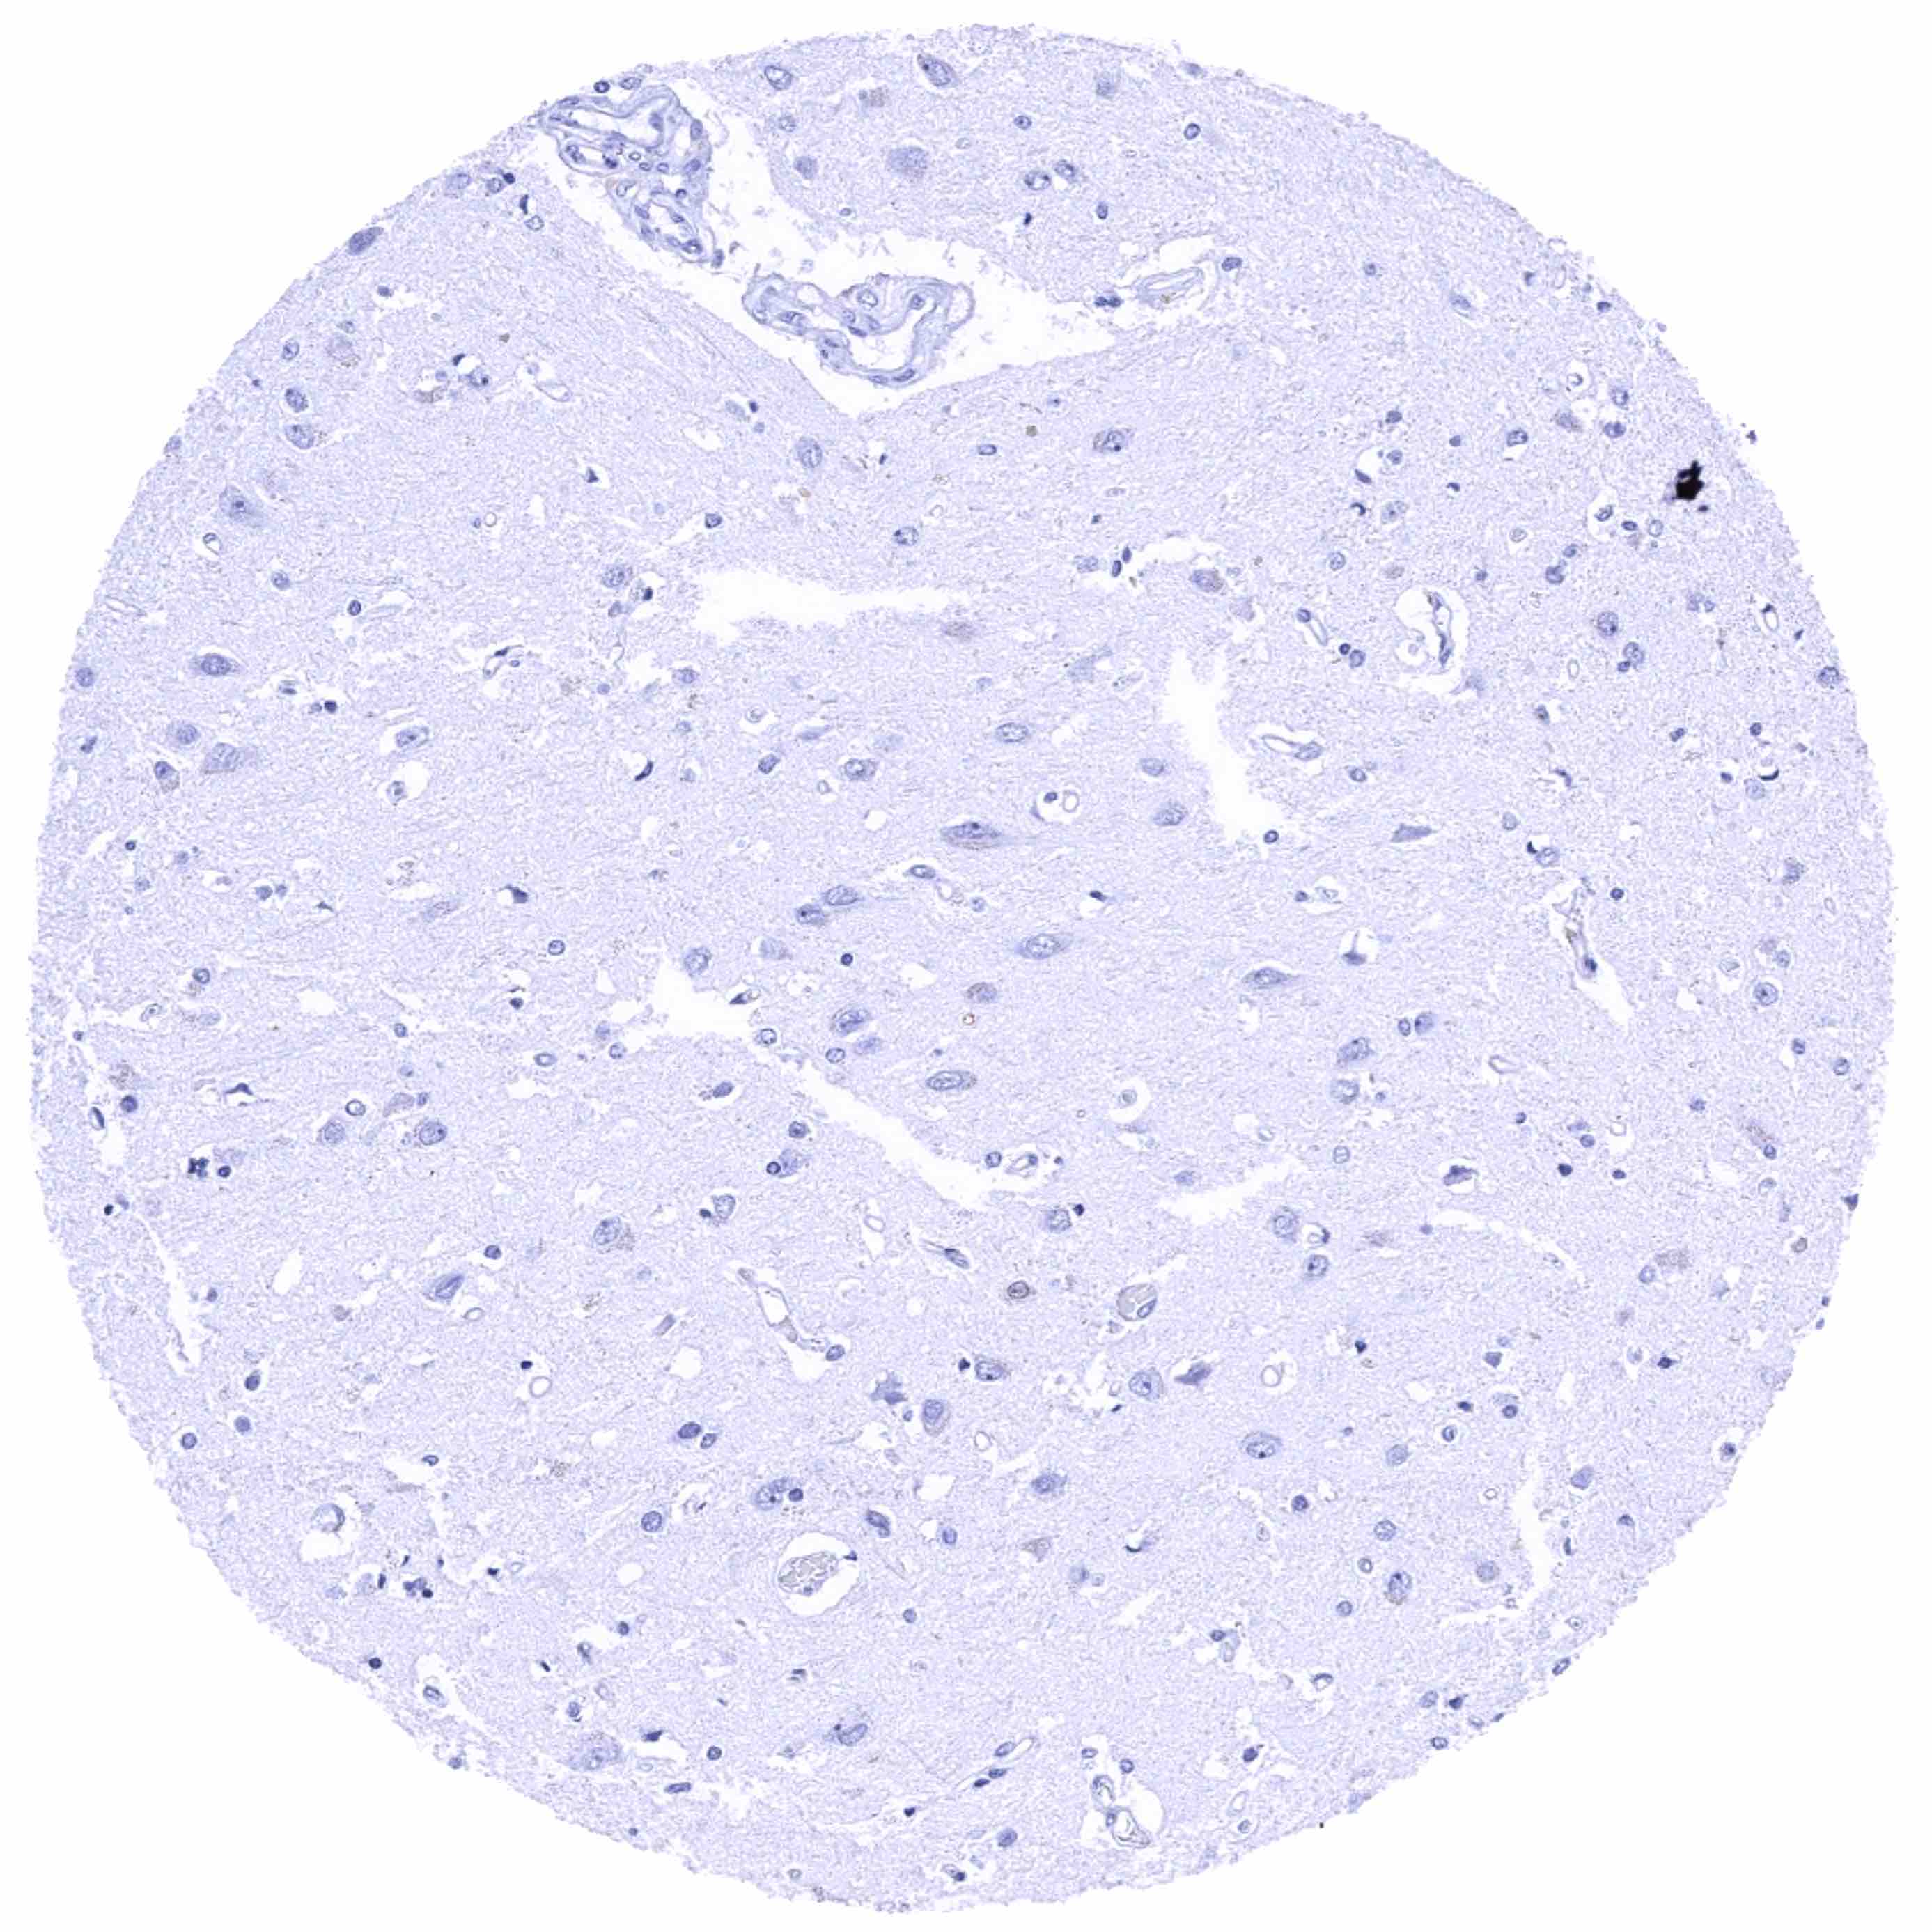

Cerebrum, grey matter

Cerebrum, white matter